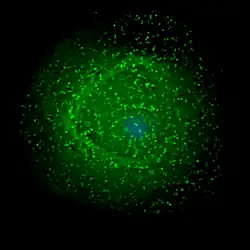

HIV assembling on the surface of an infected macrophage. The HIV virions have been marked with a green fluorescent tag and then viewed under a fluorescent microscope.

The final step of the viral cycle, assembly of new HIV-1 virions, begins at the plasma membrane of the host cell. The Env polyprotein (gp160) goes through the endoplasmic reticulum and is transported to the Golgi apparatus where it is cleaved by furin resulting in the two HIV envelope glycoproteins, gp41 and gp120.[88] These are transported to the plasma membrane of the host cell where gp41 anchors gp120 to the membrane of the infected cell. The Gag (p55) and Gag-Pol (p160) polyproteins also associate with the inner surface of the plasma membrane along with the HIV genomic RNA as the forming virion begins to bud from the host cell. The budded virion is still immature as the gag polyproteins still need to be cleaved into the actual matrix, capsid and nucleocapsid proteins. This cleavage is mediated by the packaged viral protease and can be inhibited by antiretroviral drugs of the protease inhibitor class. The various structural components then assemble to produce a mature HIV virion.[89] Only mature virions are then able to infect another cell.